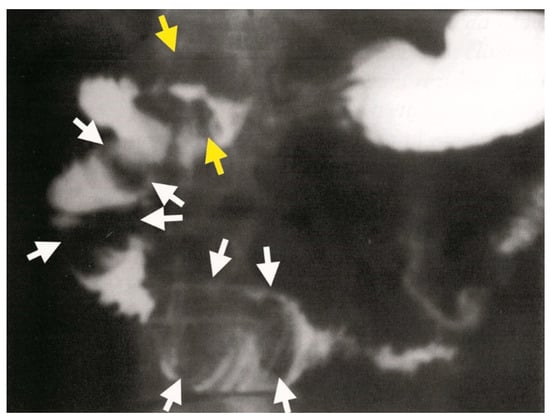

A proximal endoscopy identified a 2 cm gallstone in the duodenal bulb, which appeared yellowish-green in color. The mucosa of the posterior wall of the bulb was eroded and hyperemic, but there was no evidence of a wall defect. Further diagnostic evaluation through gastroduodenal passage imaging confirmed the presence of a duodeno-biliary fistula (Figure 7). In the duodenal bulb, oval filling defects consistent with Bouveret’s syndrome were observed, with the largest stone measuring approximately 6 cm in diameter (Figure 8).

Figure 7.

Gastroduodenal passage showing a cholecystoduodenal fistula (yellow arrow) with impacted stones in the duodenum. Oval filling defects are clearly delineated in the duodenal bulb (white arrows).

Figure 8.

Gastroduodenal passage showing multiple oval filling defects clearly localized in the duodenal bulb (yellow arrows) and extending through the D1, D2, and D3-D4 segments of the duodenum (white arrows).